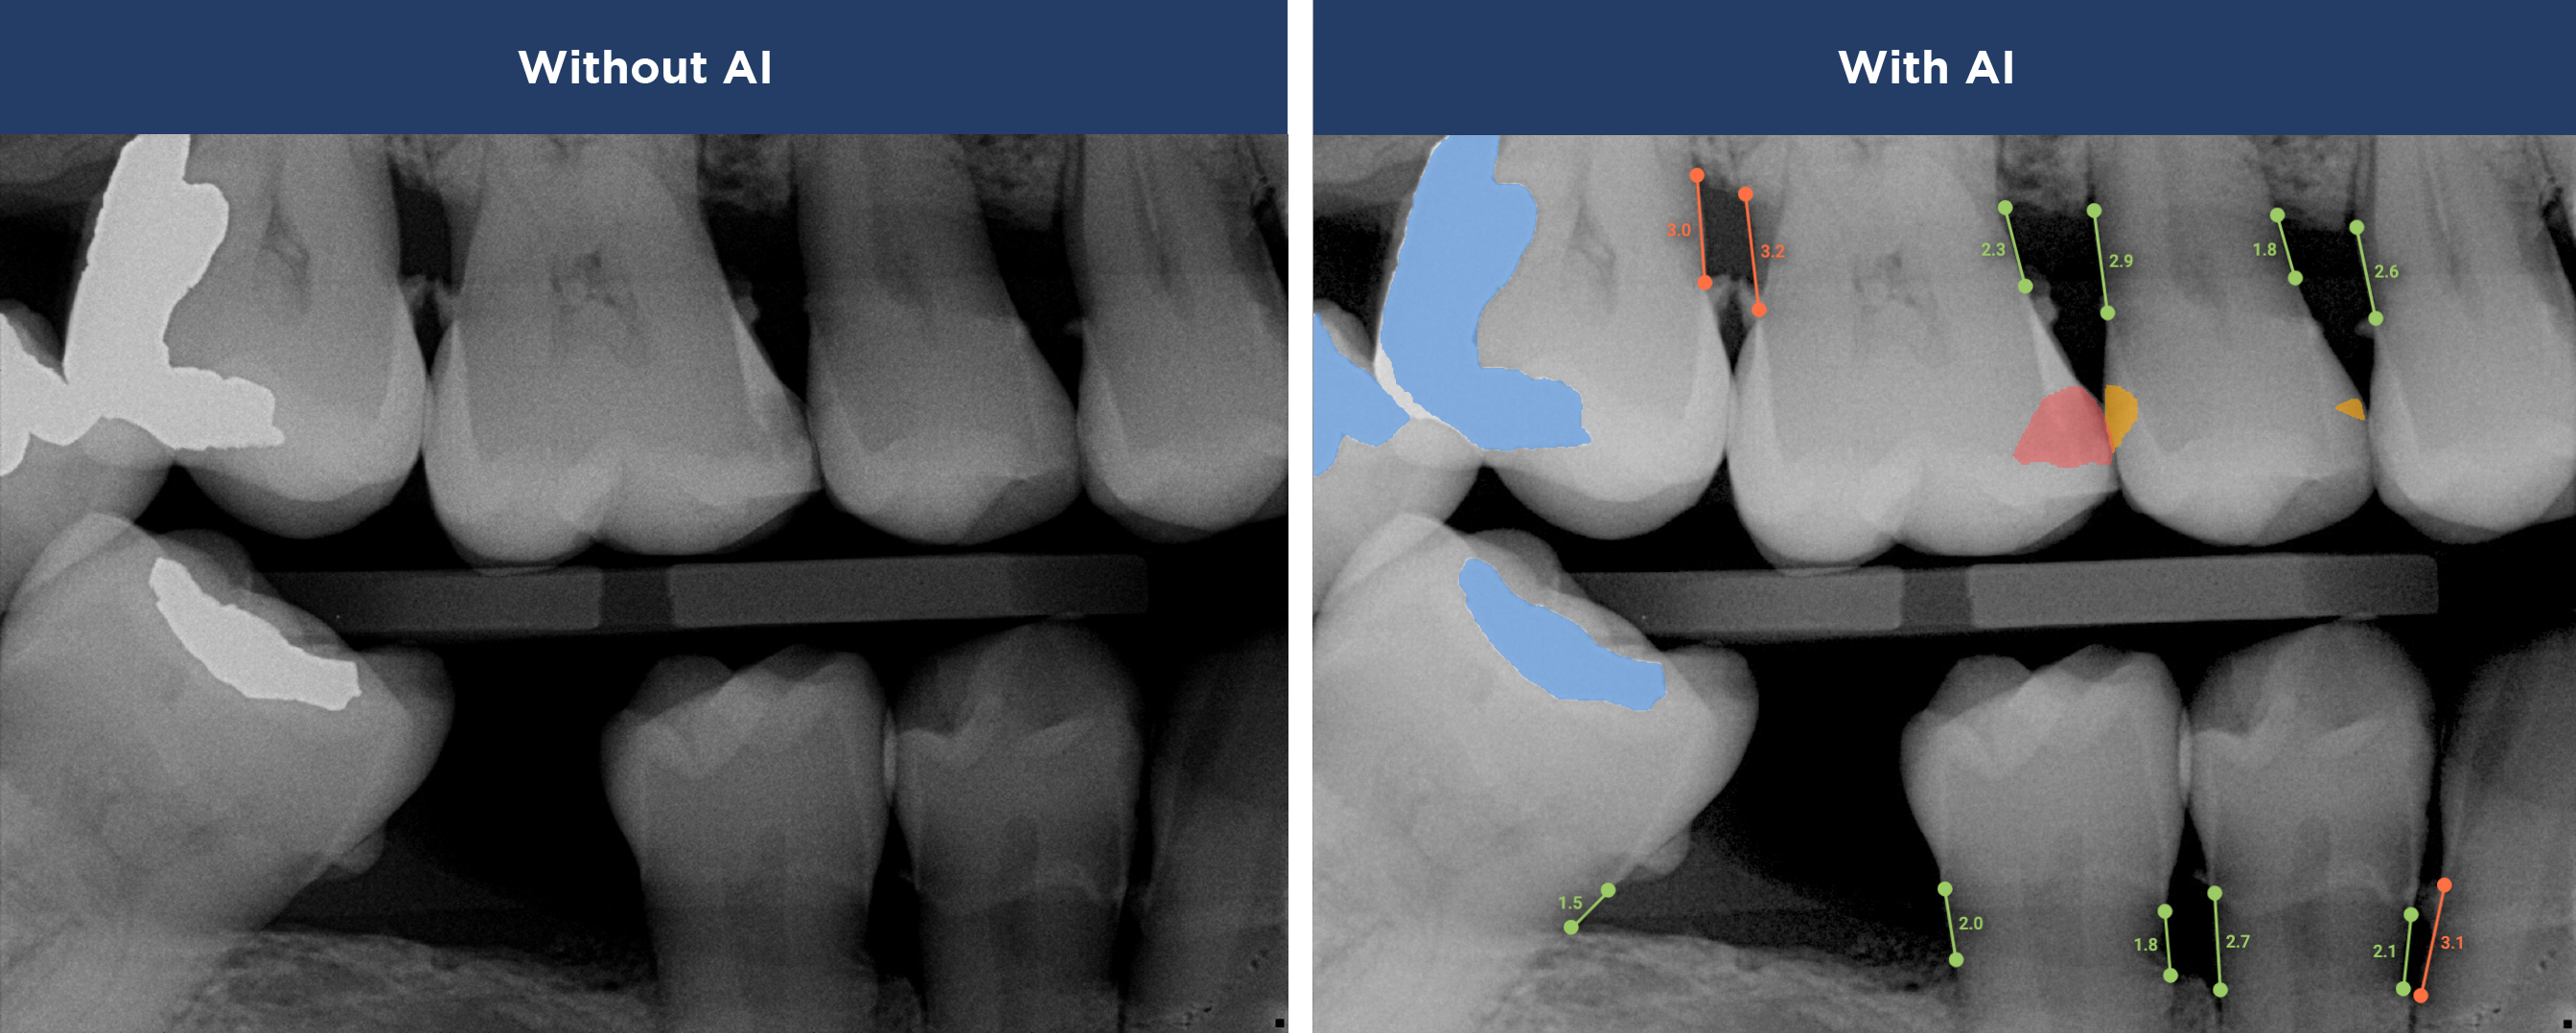

Overjet AI's  patient-centric technology combines human intelligence with the power of artificial intelligence.

Best in class dental care for every patient, on every visit.

Confidence in Your Diagnosis

Our practice is proud to provide the best technology in the dental industry, including Overjet AI for instant X-ray analysis.

Overjet’s artificial intelligence technology transforms traditional black-and-white X-rays by adding a layer of data that instantly outlines decay (cavities) and measures bone loss. This makes it easy for you to see your results alongside your dentist.  It’s like getting a second opinion delivered instantly. With Overjet’s analysis and easy-to-read presentation, you will have the information you need to make an informed decision about your oral health. Together, we’ll review your findings and discuss the best steps to take to achieve your goals.